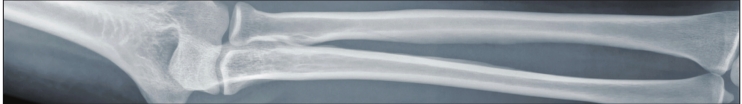

“Especially when you’re older, broken bones due to osteoporosis are most likely to occur in the hip, spine and wrist, but other bones can break, too,” she said. “Broken bones can cause severe pain that may not go away. With osteoporosis some people lose height and become shorter. It can also affect your posture, causing you to become stooped or hunched.”

When diagnosing for osteoporosis, Walton states that a bone density test is the only test that can diagnose for the disease before a broken bone occurs.

“This test helps to estimate the density of your bones and your chance of breaking a bone,” she said. “The NOF [National Osteoporosis Foundation] recommends a bone density test of the hip and spine by a central DXA [dual energy X-ray absorptiometry] machine to diagnose osteoporosis.”